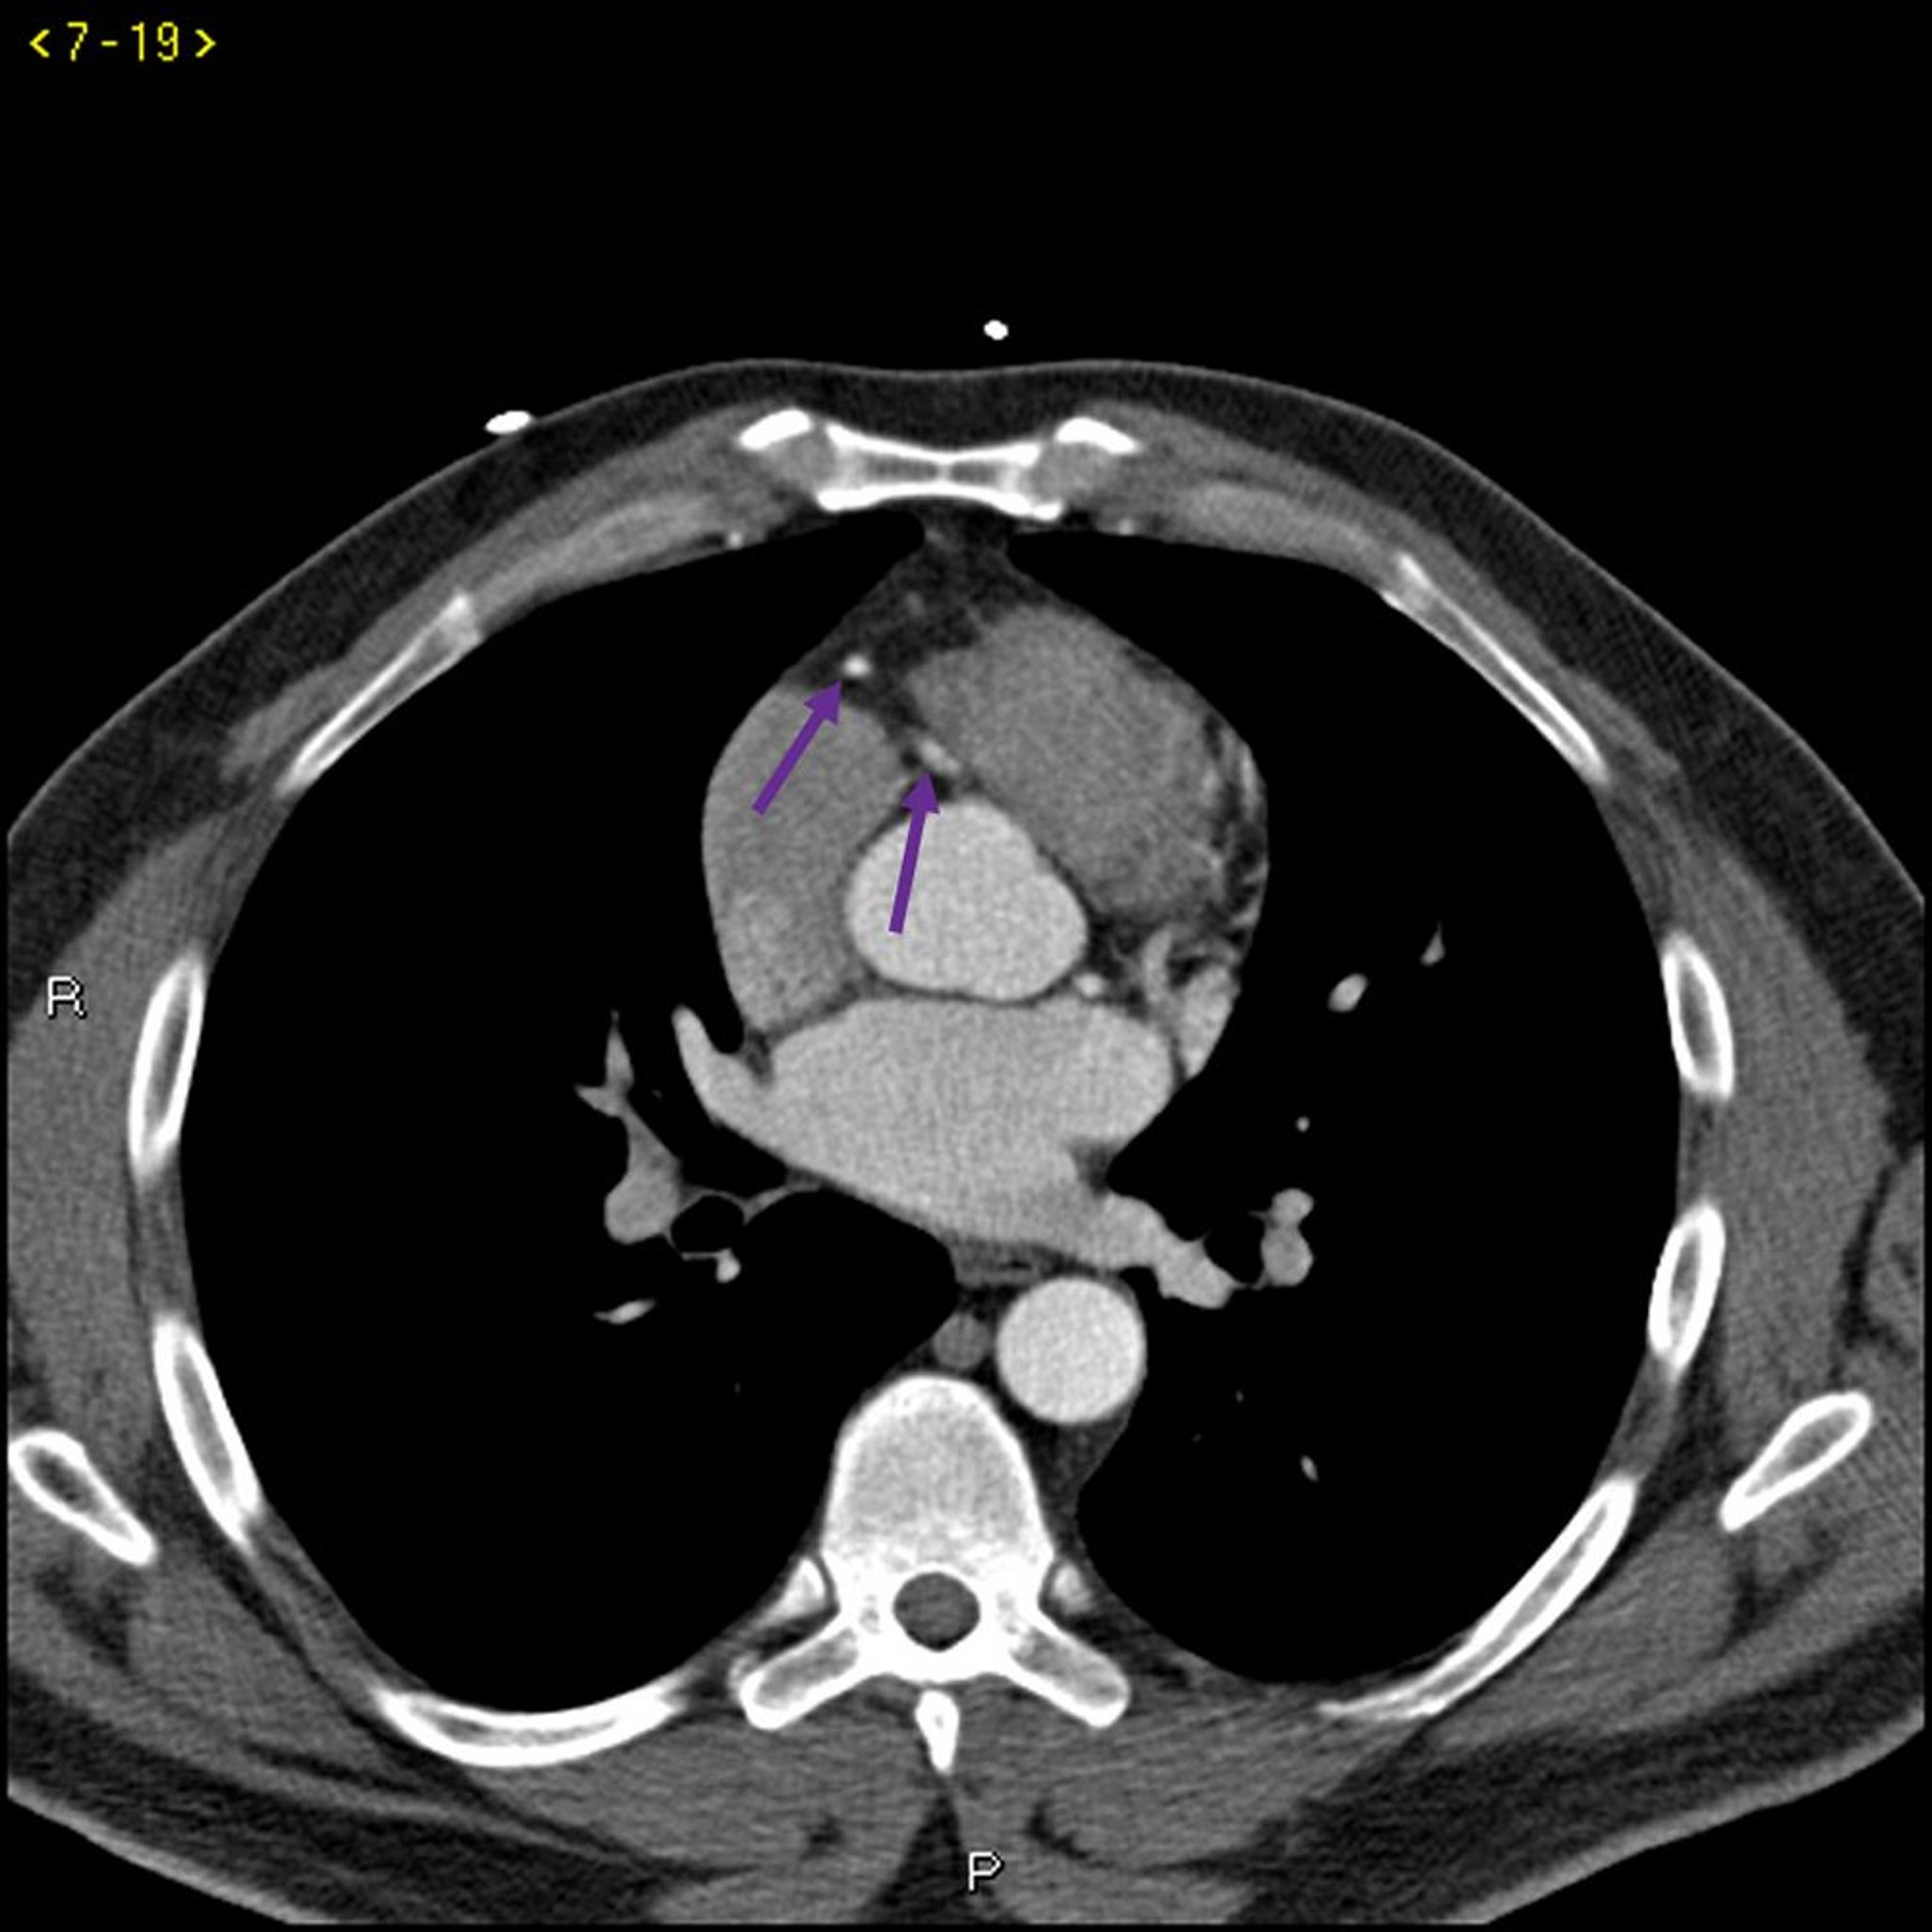

Tomografía computarizada con contraste que muestra arterias coronarias normales–diapositiva 4

Esta TC con contraste muestra arterias coronarias normales. La arteria principal izquierda está indicada por la flecha roja. Las arterias descendente anterior izquierda y circunfleja izquierda están indicadas por las flechas verde y azul respectivamente, y la arteria coronaria derecha está indicada por la flecha púrpura.